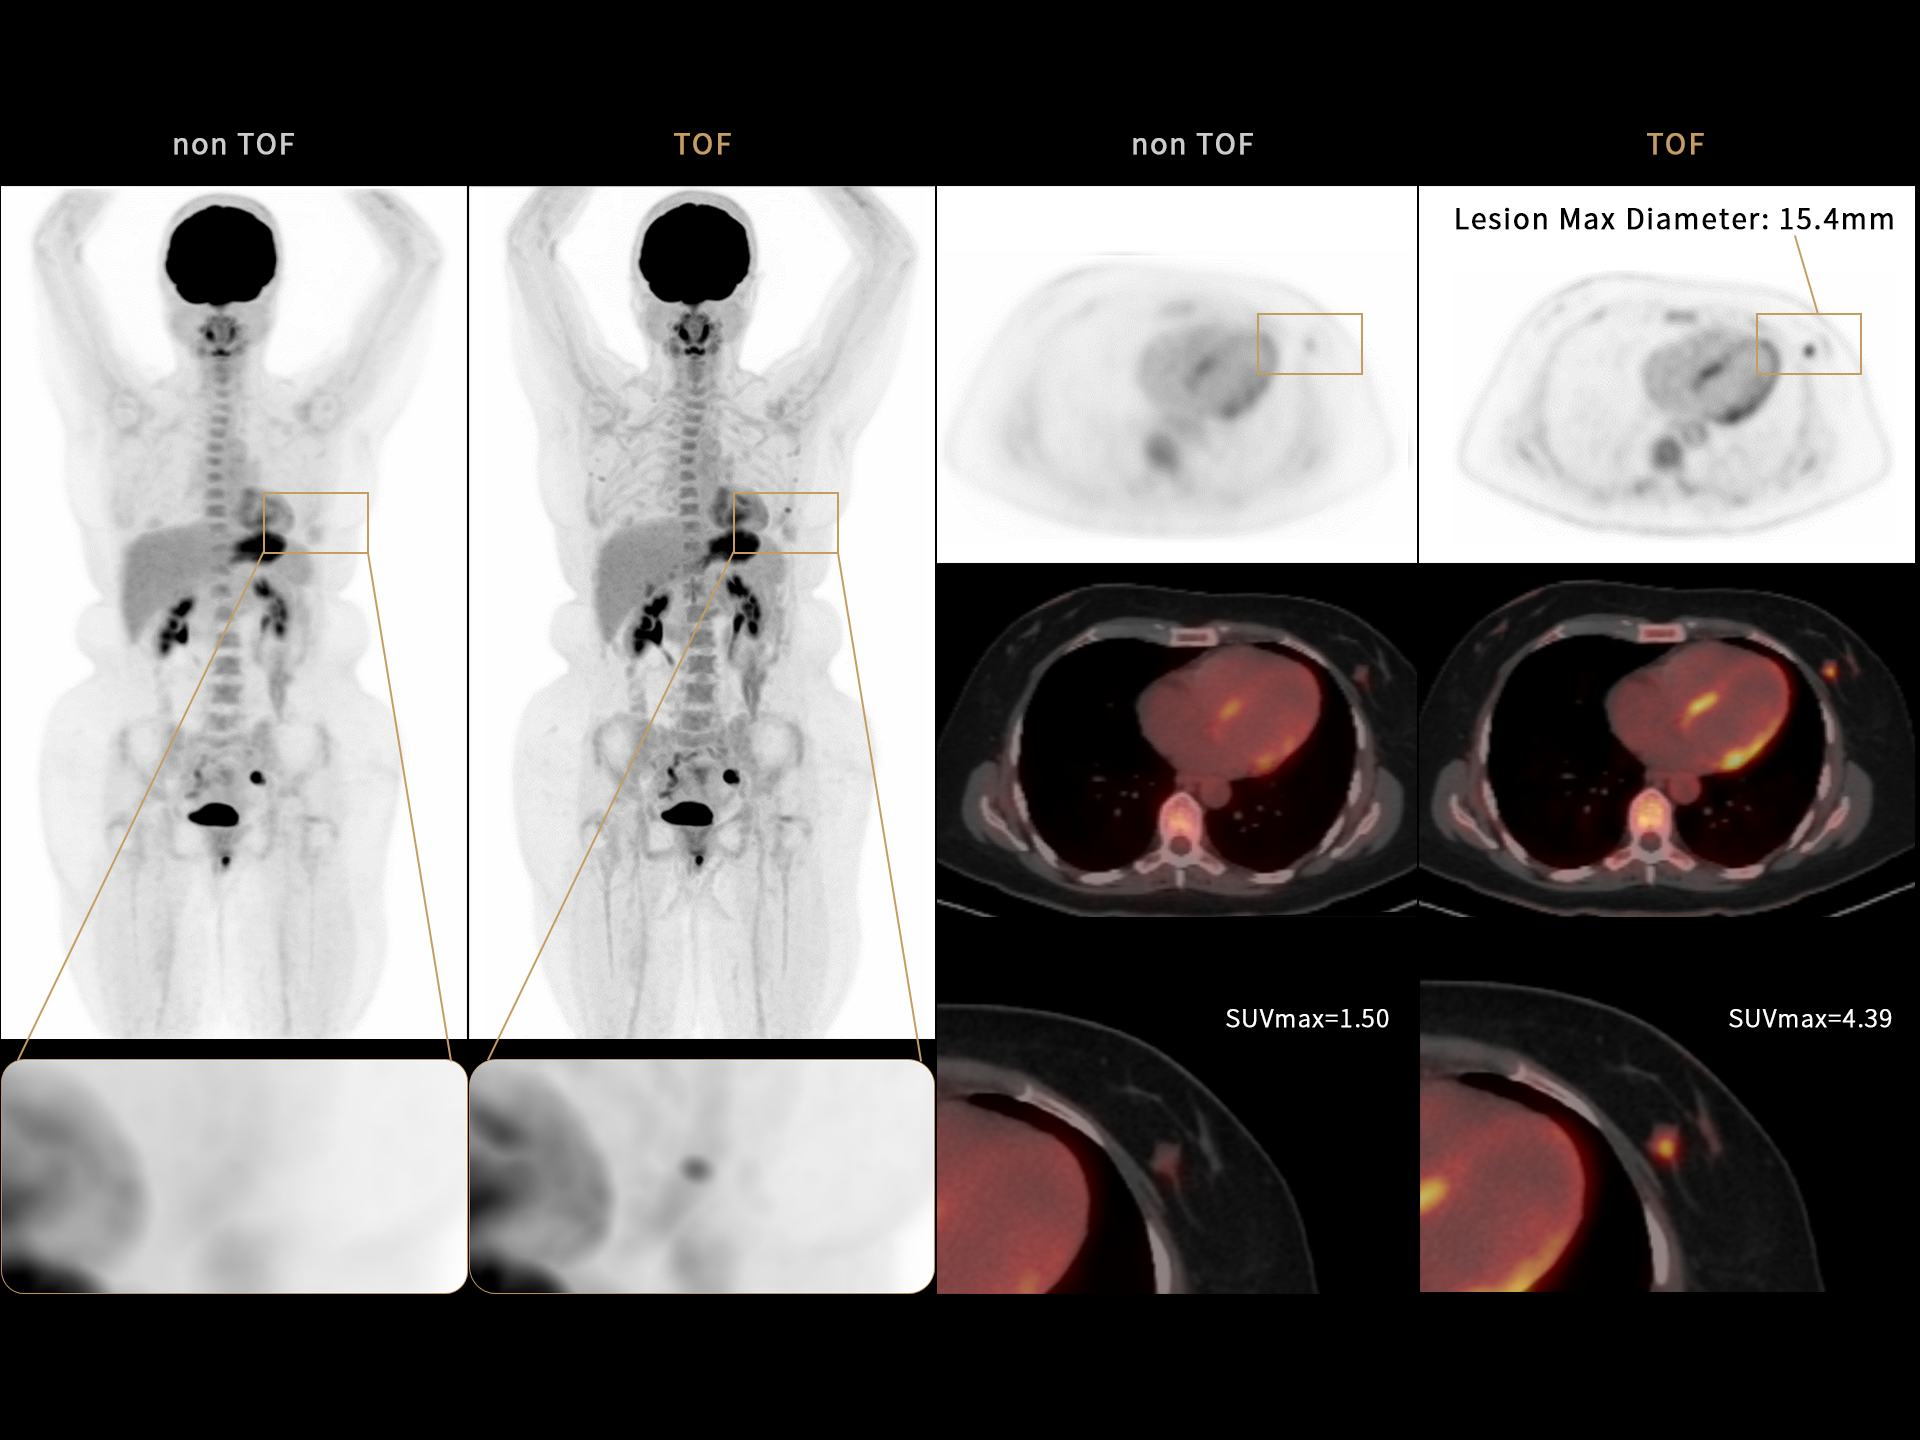

181 cps/kBq and more¹

High effective sensitivity that benefits from TOF gain leverages better diagnostic accuracy under low dose usage and fast scan time.